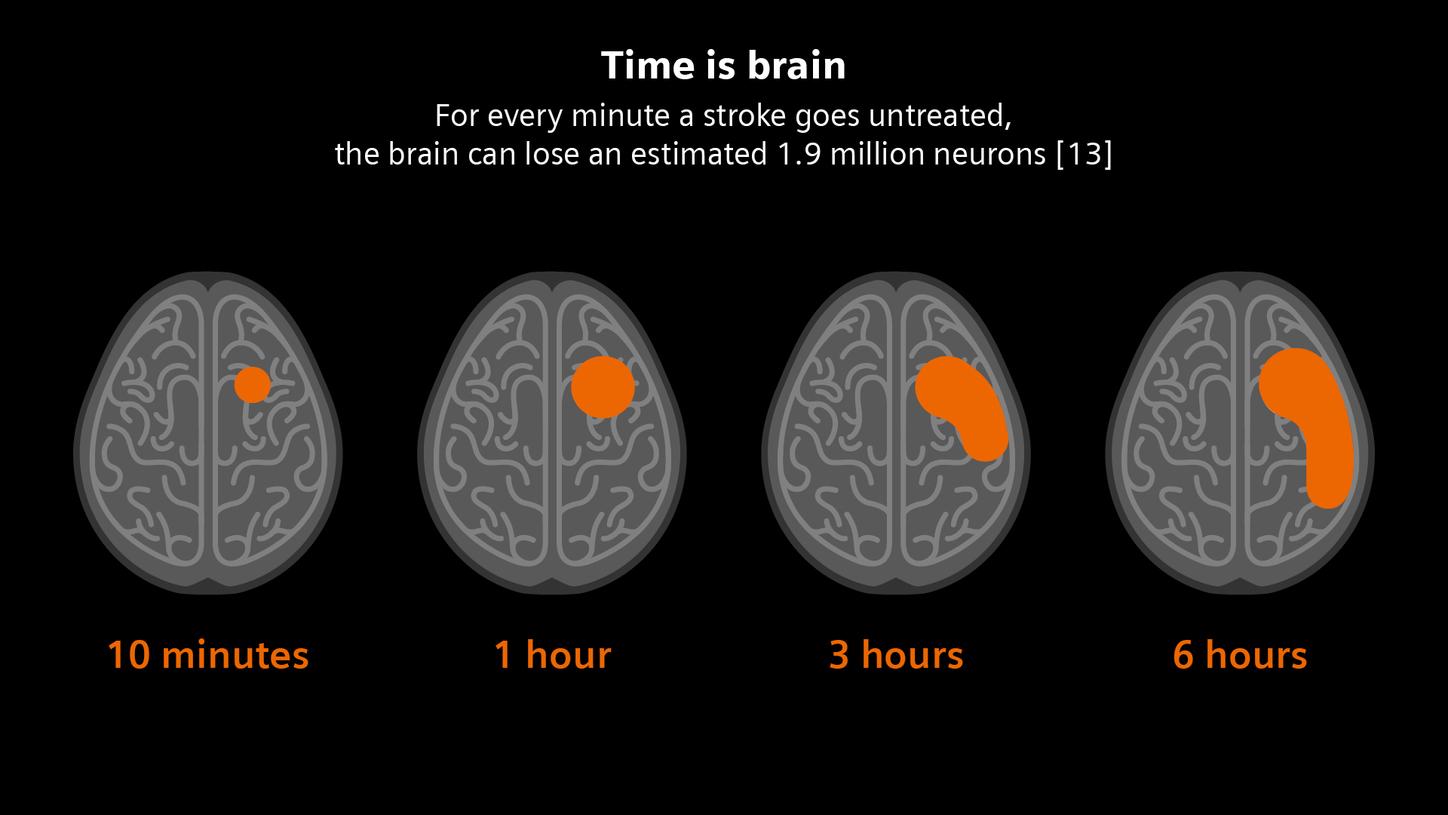

In stroke care, time is brain. Rapid and accurate imaging is crucial to assess the extent of brain injury and guide immediate treatment. Angiography, MRI, CT, ultrasound, and lab diagnostics are essential tools in identifying stroke type, location, and severity. Advances in imaging technology now allow for even faster acquisition, improved resolution, and enhanced visualization of brain tissue and blood vessels. Innovations such as perfusion imaging, real-time vascular mapping, and AI-assisted diagnostics are transforming stroke workflows and enabling precise, timely interventions.

[13] Saver JL. Time is brain--quantified. Stroke [Internet]. 2006;37(1):263–6. Available from: http://dx.doi.org/10.1161/01.STR.0000196957.55928.ab